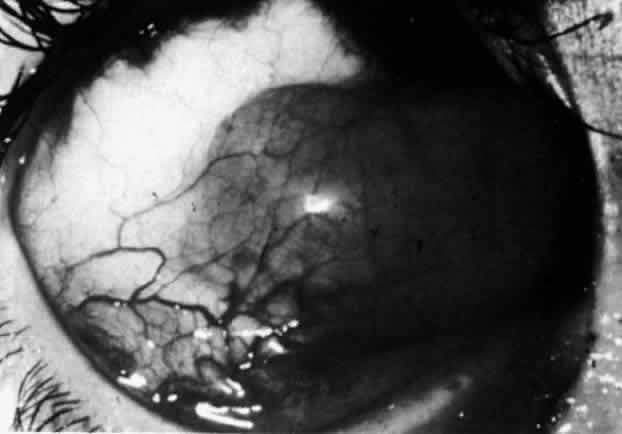

Simple and nodular episcleritis differ in their clinical courses, but in both the edema and infiltration are entirely within the episcleral tissues. The sclera is not involved. The maximum congestion is in the superficial episcleral network, with some slight congestion of the conjunctival vessels and deep episcleral vessels (Fig. 10). The intraocular structures are not involved in either variety, nor is the visual acuity affected. Anterior segment fluorescein angiography reveals a normal vascular pattern but a very rapid flow rate, with the whole transit of the dye being completed within 2 or 3 seconds (Figs. 11 and 12).

Fig. 10. Maximum congestion in the superficial vascular plexus in episcleritis. The conjunctival and deep episcleral networks are separated from the deep plexus by edema and infiltration in the episcleral tissue. (Watson PG, Hayreh S, Awdry P: Episcleritis and scleritis. Br J Ophthalmol 52(3):278–279, 1968)

Fig. 11. Anterior segment fluorescein angiogram of a 45-year-old woman with simple episcleritis. At first transit of dye, all the vessels are dilated and filling simultaneously. However, the vascular pattern is not disturbed.

Fig. 12. Angiogram of the same 45-year-old woman in Figure 11 one second later. Within 1 second, all the vessels are filled and there is even, venular filling except in the deep episcleral plexus. This is the rapid filling pattern seen in all forms of episcleritis and in diffuse anterior scleritis.

The redness of simple episcleritis may be intense, varying from a fiery-red or a brick-red discoloration to a mild red flush, but it does not have the bluish tinge that is seen in scleritis. The distribution is usually sectorial but can involve the whole anterior segment of the globe. The episcleral vessels are engorged but retain their normal radial position and architecture (Figs. 13 and 14; Color Plate 1A). In simple episcleritis, there is a diffuse edema of the episcleral tissues. These tissues are sometimes infiltrated with gray deposits that appear yellow in red-free light. Surprisingly, the eye is rarely tender to the touch.

Fig. 13. Infiltration of the episclera in which the superficial episcleral vessels show maximal congestion. Conjunctival vessels are slightly congested, as is the deep episcleral plexus, whose irregular criss-cross pattern can be seen deep to the radially arranged superficial episcleral plexus.

Fig. 14. Diffuse inflammation. Superficial vessels are maximally engorged and retain their radial pattern and architecture. (See Figures 27 and 34.) (Watson PG: Connective tissue disorders and the eye. In: Recent Advances in Ophthalmology, Vol 5, pp 214–277. London, Churchill-Livingstone, 1975)